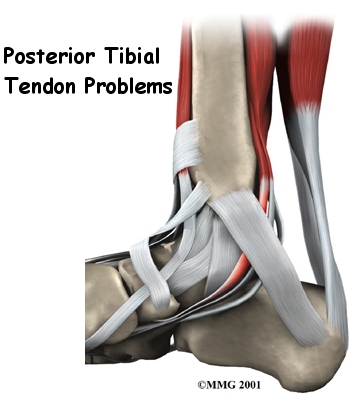

Anatomy

Where is the posterior tibial tendon, and what does it do?

The posterior tibial tendon runs behind the inside bump on the ankle (the medial malleolus), across the instep, and into the bottom of the foot. The tendon is important in supporting the arch of the foot and helps turn the foot inward during walking.

Problems with the posterior tibial tendon seem to occur in stages. Initially, irritation of the outer covering of the tendon, called the paratenon, causes paratendonitis. This means that there is inflammation between the lining of the tendon and the tendon itself where it runs through the tunnel behind the medial malleolus. This tendonitis can start a process of wear and tear on the tendon fibers.